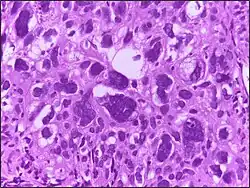

![]() |

Hodgkin's lymphoma | Micrograph of a lymph node in Hodgkin's lymphoma with the characteristic Reed-Sternberg cell. RS cell is a large cell with abundant amophophilic cytoplasm and binucleate mirror image nuclei. Each nucleus contains an acidophilic nucleolus surrounded by a halo. | Category: Histopathology of Hodgkin's lymphoma | Hodgkin's lymphoma |